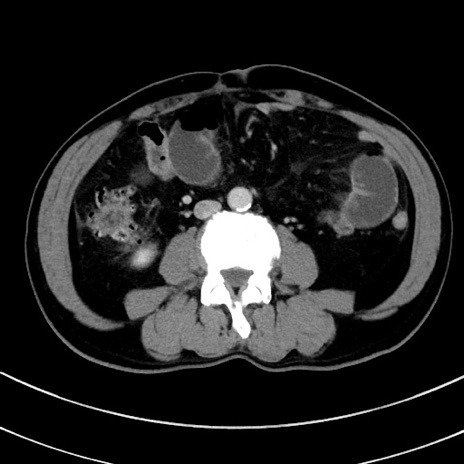

症例8(横断像)

【症例】 60歳代男性

【主訴】 黒色吐物

【現病歴】 4日前から嘔気自覚、2日前の朝食後にも嘔気あり、自分で手で嘔吐反射起こし嘔吐したところ血が混ざっていたため受診。

【既往歴】 5年前汎発性腹膜炎を伴う急性虫垂炎で手術、高血圧、前立腺肥大症、高脂血症

【身体所見】 腹部正中に手術癩痕あり 腹部平坦・軟圧痛なし膨満感あり

【データ】WBC 8400、CRP 4.54